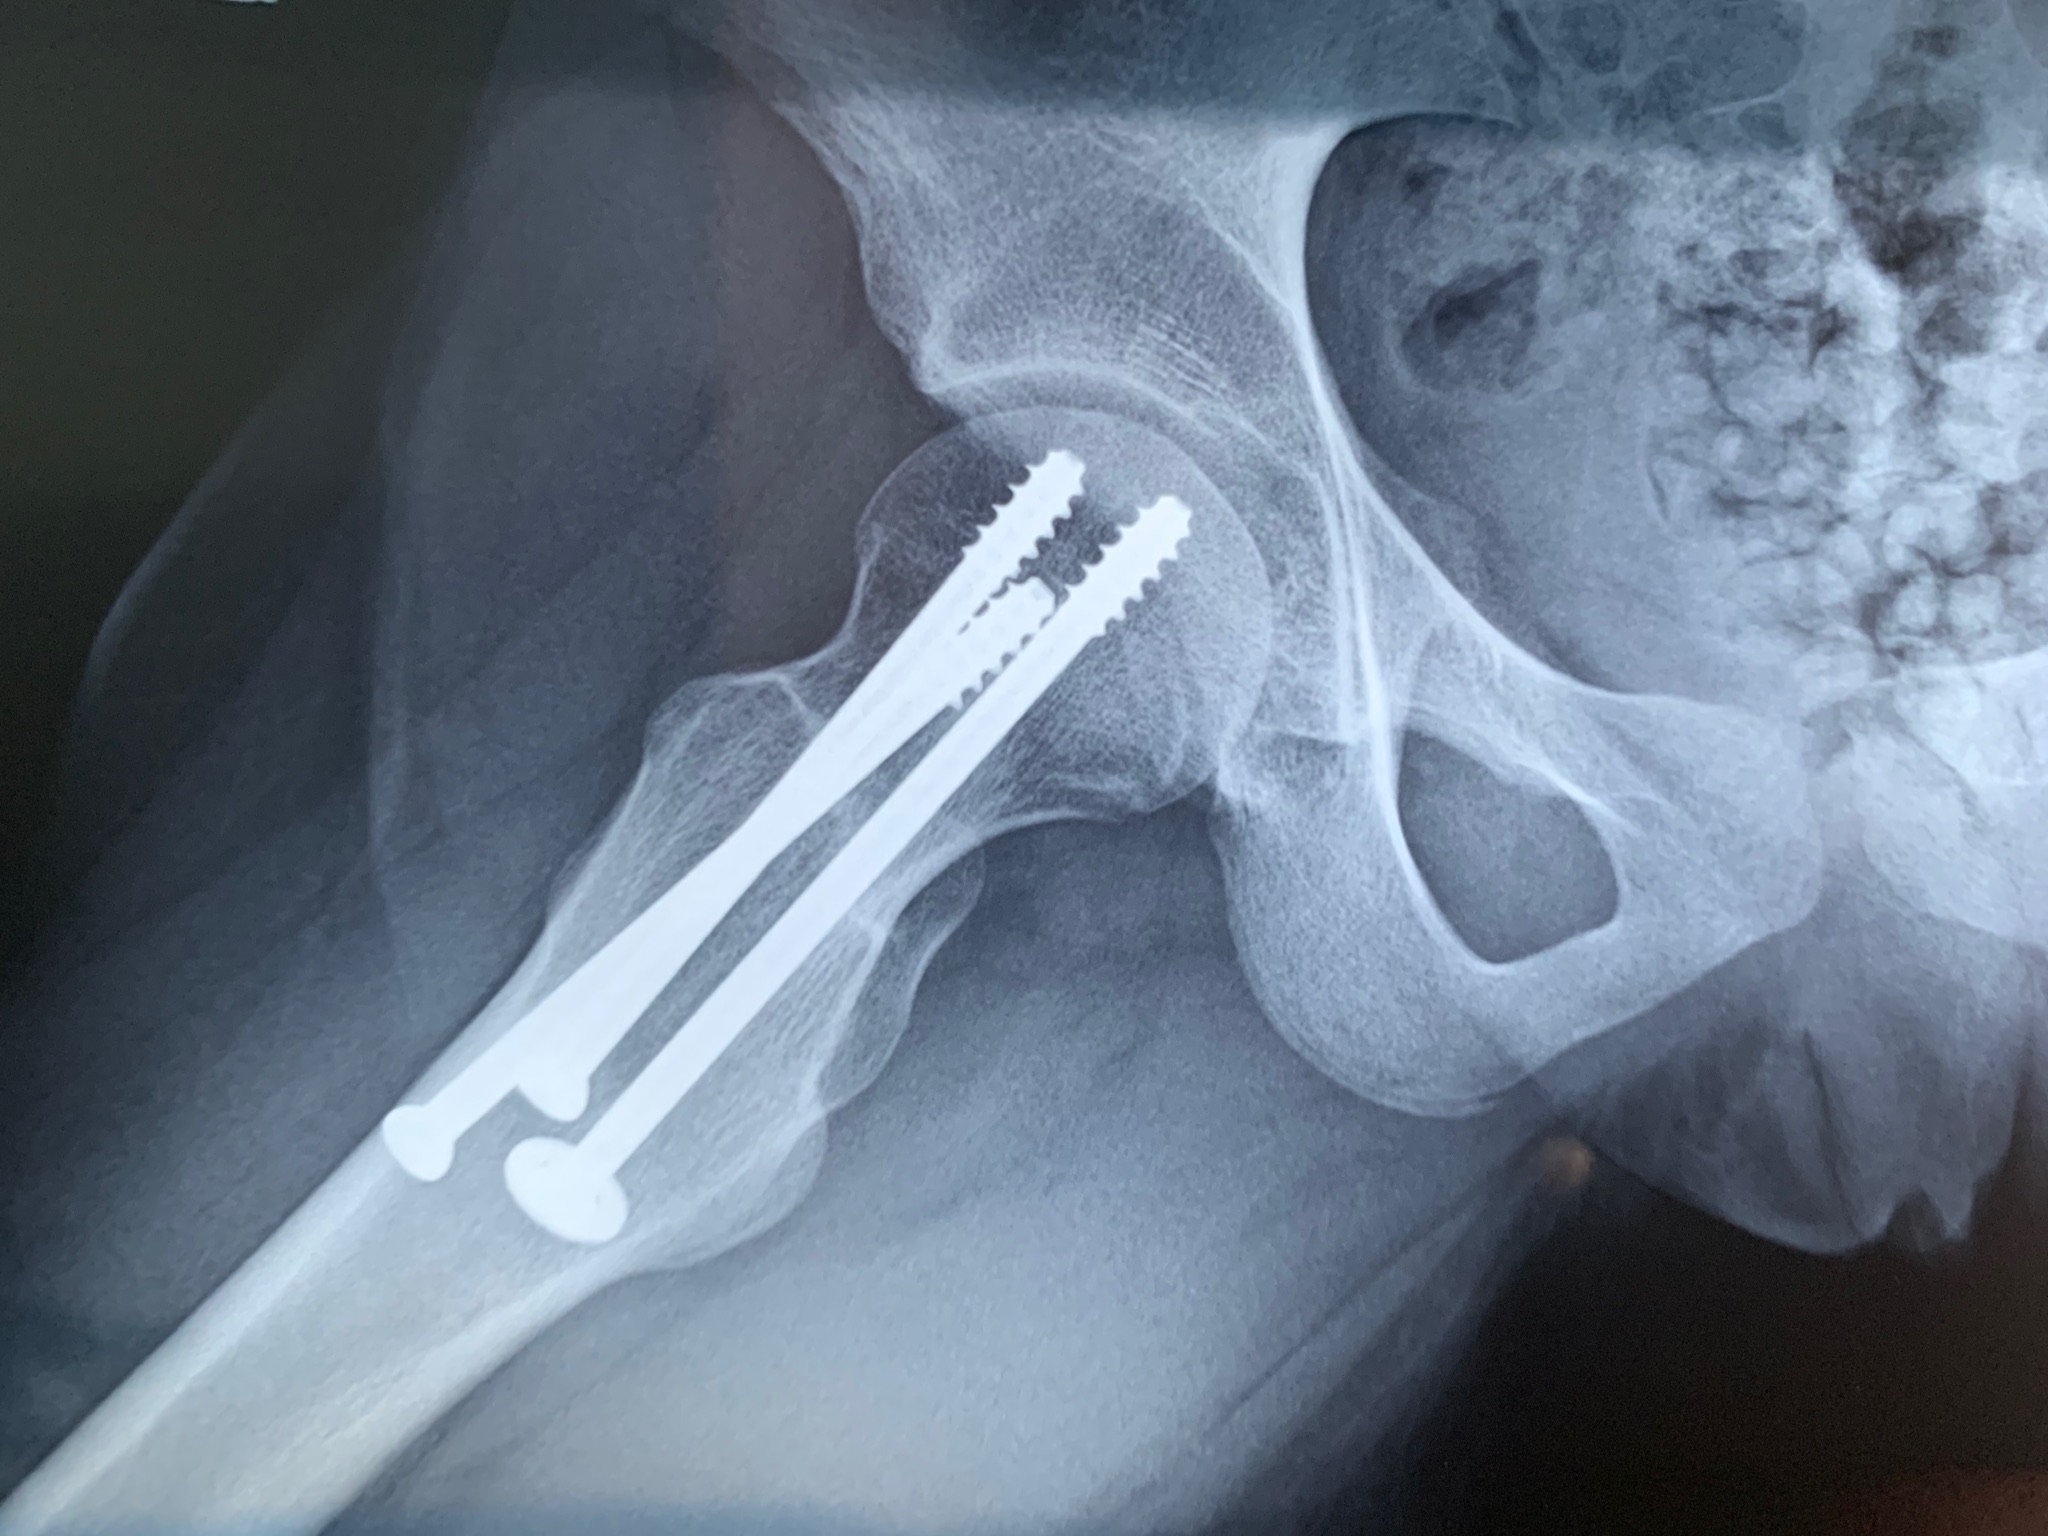

Mia figlia, oggi quattordicenne , un anno fa cadendo ha rotto il collo del femore.È stata operata immediatamente e le sono state inserite 3 viti. È ormai passato un anno e abbiamo eseguito i controlli di routine.

Il collo del femore fratturato è guarito perfettamente, non si parla di rimozioni delle viti di sintesi, mi chiedo se invece, considerando consolidata la frattura, perché conservare 3 viti, all’interno dell’osso se effettivamente non servono e anche se un domani succedesse qualcosa ci sarebbero sempre le tre viti...

DB977FD6-6AD4-4951-93A5-89D8362A9035.jpeg

[ 477.12 KiB | Osservato 1100 volte ]